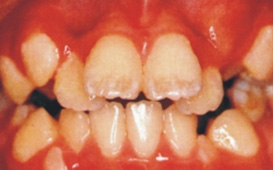

許多人有「牙齒不整齊不是病」的錯誤觀念,同時,認為矯正治療只是個改進美觀的「美容整型治療」 ; 固然齒列矯正治療可以有效的促進臉部的美觀,但齒列不整可同時產生功能與健康的問題,臨床資料明顯顯示,齒顎不整的病者易產生蛀牙及牙周病,但因為這類疾病是個慢性與漸進的,發病初期並無明顯感覺,它因此造成許多人疏於治療,當發病時已相當嚴重。 因此,齒列矯正治療並非只是美容治療,它實質上可同時促進咬合功能與口腔的健康。